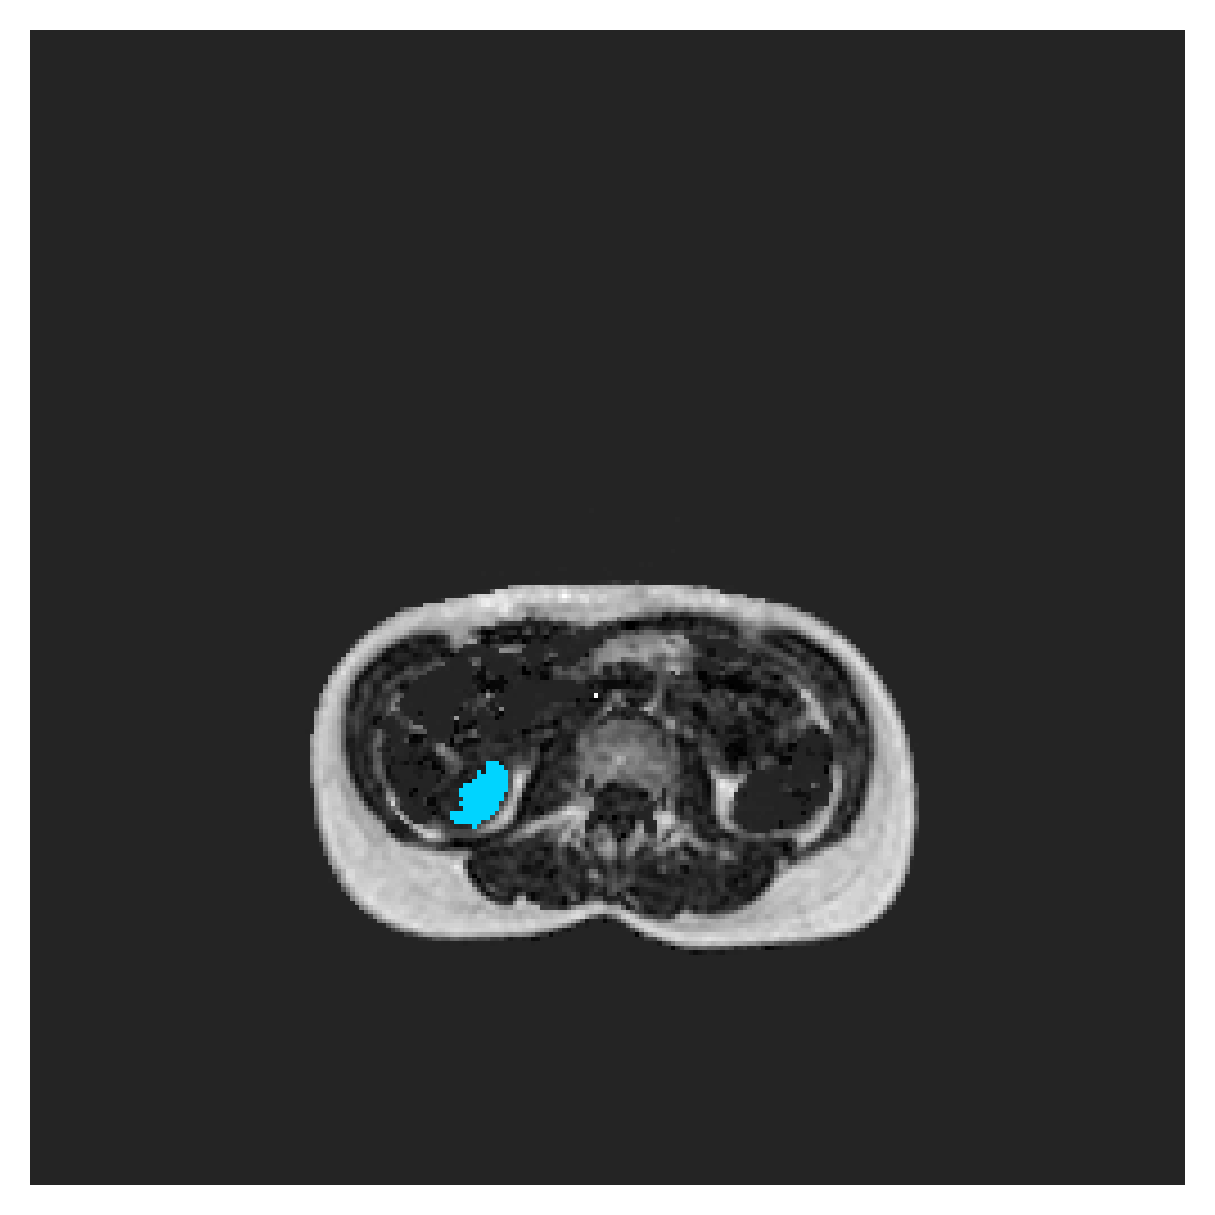

POEM

The Prospective investigation of Obesity, ENergy production and Metabolism (POEM) is a local (not currently publicly available; PI: L. Lind, see [22] for details) cohort of whole-body fat/water separated MR images. Full annotations of the liver, kidneys, bladder, pancreas and spleen are available for 50 subjects, providing a challenging segmentation dataset with heavily imbalanced classes of varying shapes. The resolution of the data is anisotropic, with reconstructed voxel size of in left-right, anterior-posterior and foot-head directions, respectively. For additional technical details regarding the acquisition and specifications of the images see [22].

The images contain two channels, one for water and one for fat content. For training, we normalize the volumes (per channel) and use 2D slices in the coronal plane, sized . The weak annotations are created synthetically, following the same procedure as described for the ACDC dataset.

5.2 Abdominal organ segmentation

Using 2D distance maps

In Table 3, the average DSC and HD95 results are shown (both using 2D and 3D distance maps) for the task of abdominal organ segmentation in POEM data (for boxplots see figures 8 and 9). We see that training with and (with distances calculated on 2D slices) performs comparably, while using and produces lower scores in both DSC and HD95 metric. On this dataset, the CRF-loss is able to compete with the boundary loss-based training strategies, even outperforming them on most classes. Most notably, all models trained with boundary loss appear to have a hard time segmenting the liver. We hypothesize this may be due to extremely severe class imbalance, as the liver covers a very large area compared to the rest of the classes. It is thus also more strongly affected by undersegmentations.

Using 3D distance maps

Inspecting the values of training with on distance maps computed in 3D from Table 3, we notice that the results generally improve over values achieved by using 2D distance maps. Most notable decreases are visible in HD95 values, as using volume-calculated distance maps provides more global information and additionally penalizes spatially unreasonable segmentations. The methods based on are now able to compete with the CRF-loss, in particular the one.

In Figure 10, the validation curve evolution is plotted. Comparing it to the one with using 2D-computed distance maps, in Figure 7, we see that the curves for all the methods training with improve, with the exception of based one. The lack of improvement here could be attributed to the MBD bleeding through object boundaries (due to noise) and propagating low distances further away in the volume, causing under-penalization. This is also suggested by the degradation in performance from 2D to 3D maps in Table 3. But at the same time, it allows for better segmentation of large and/or elongated (homogeneous) objects, which is also confirmed by the large improvement of liver segmentation scores in Table 3.

5.2.1 Qualitative comparison

In Figure 11 and 12 we show the same random slices in cases of calculating the boundary loss on 2D- and 3D-based distances, respectively. Comparing the two figures again indicates that the intensity-aware distances offer most improvement when calculated in 3D over 2D. The exception here is the MBD, which seems to even slightly degrade for most classes.